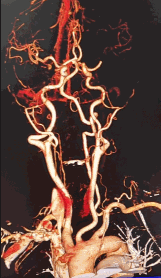

术前CTA提示左侧大脑中动脉M1段闭塞。

90cm Locaste 088输送导管建立路径,造影提示左侧大脑中动脉M1段闭塞。